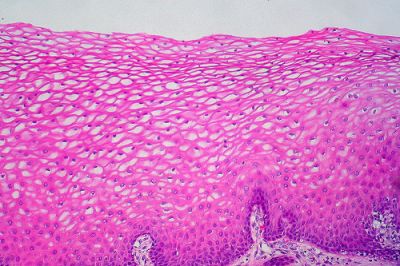

- Acanthosis - merülés ekzotserviksa laphám a mögöttes szerkezetét. Önmagában, ez nem káros, de kísérhetik egyéb patológiás folyamat.

- Atipikus metaplasticus hám - jele a rossz biopszia. Ez azt jelenti, hogy ahelyett, hogy a szokásos nyaki hám tartalmaz szokatlan szerkezetek, amelyek nem kellene itt lennie.